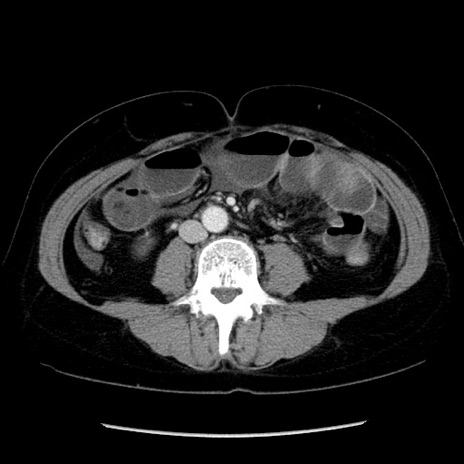

冠状断像

矢状断像